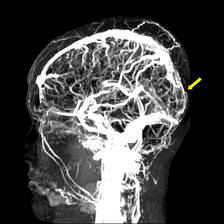

Courtesy of Dr. Gustavo Saposnik

Magnetic resonance venography shows thrombosis of the superior sagittal sinus.

The guidelines include an algorithm for diagnosing and managing cerebral venous thromboembolism (CVT), which is caused by a clot in the dural venous sinuses, veins that drain blood from the brain toward the heart. The guidelines were released Feb. 3 online in advance of publication in Stroke.

If a clinician suspects CVT, either MRI or magnetic resonance venography (MRV) is recommended to make the diagnosis by showing a thrombus obstructing the venous sinuses or cerebral veins. In emergency departments, either a CT scan or CT venography can be used if MRI is not available. "This allows different clinicians to initiate the appropriate work-up in the acute setting," Dr. Saposnik said.